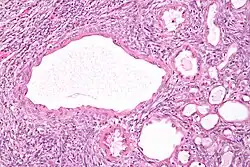

The characteristics of cystic nephromas are:

- Cysts lined by a simple epithelium with a hobnail morphology, i.e. the nuclei of the cyst lining epithelium bulges into the lumen of the cysts,

- Ovarian-like stroma that has a:

- Spindle cell morphology, and has a

- Basophilic cytoplasm.

Micrograph of a cystic nephroma. H&E stain.